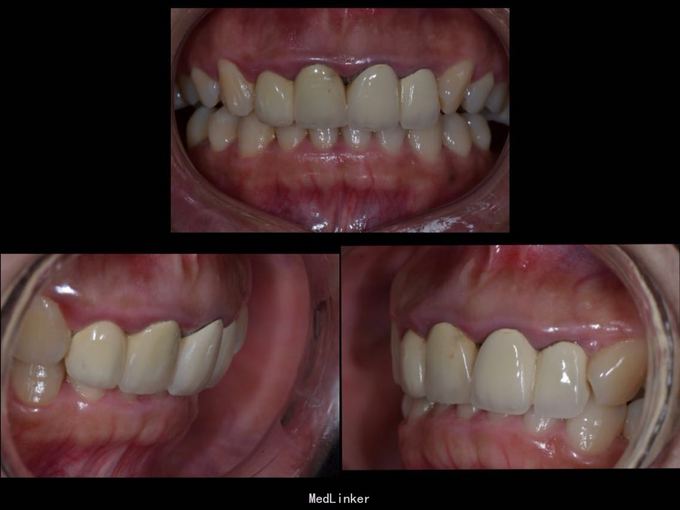

上门牙外伤金属烤瓷冠修复七年,牙龈发黑,红肿,有异味,颜色黄不美观,其他牙也黄不美观,要求重新修复

11 12 21 22金属烤瓷冠修复,牙龈发黑,冠颈部牙龈萎缩红肿有黑褐色腐质物,探出血,叩(-).23近中颊侧扭转倾斜.36 37 46 47残根,松动轻,全口牙结石中度,牙齿颜色偏黄,全景片示,11 12 21 22根管治疗不完善,根尖低密度影,有金属桩修复

11 12 21 22死髓牙,不良修复体,牙龈炎 36 37 46 47残根 牙列不齐 处置:全口洁治。 比色,拍照,取模型做蜡型。 拆除旧修复体,拆桩核,做根管治疗,纤维桩修复,牙体预备,取模,做临时冠,粘固。11 12 21 22全瓷冠修复,13 14 23 24 31 32 33 34 41 42 43 44瓷贴面修复。